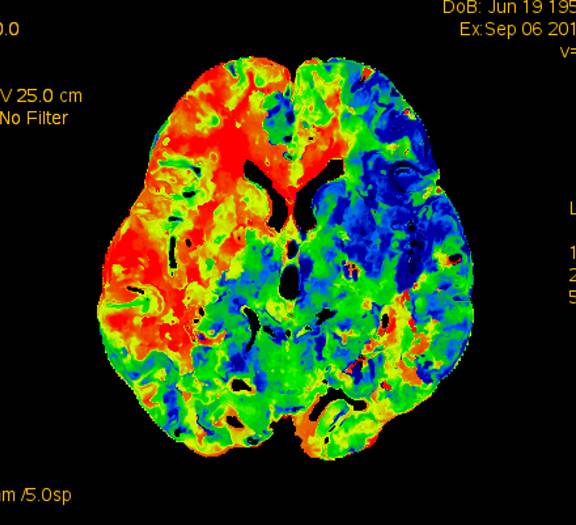

术前灌注成像,右侧大脑半球灌注较差。

术前造影:右侧颈总动脉起始部显影,其余部位闭塞。颈外动脉向颈内动脉代偿供血。

此次分享两例颈动脉闭塞复合手术开通病例。第一例为颈内动脉长段闭塞,从颈内动脉起始段开始闭塞。患者术前存在眼动脉缺血事件及右侧半球灌注不足。颈内动脉剥脱后,颈内动脉可淡淡显影,为微导管通过创造条件。微导管通过后,顺利完成球囊扩张及支架植入,完全开通右侧颈内动脉。第二例为右侧颈总动脉闭塞患者,虽有颈外动脉代偿,但仍存在TIA及右侧大脑半球灌注不足。经颈动脉内膜剥脱后,造影可见颈总动脉显影,但管腔严重不规则,经球囊扩张及支架植入后,颈总动脉显影好。两例患者术后7天复查颈动脉CTA,均显示颈内动脉起始处较术后造影增粗。